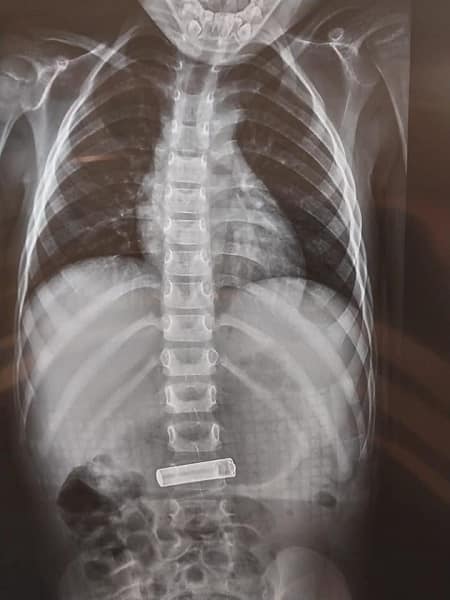

استخراج بطارية ريموت من معدة طفل

تمكن فريق طبي أردني في أحد المستشفيات الخاصة في العاصمة الاردنية عمّان، من استخراج بطارية ريموت، من معدة طفل.

وفي التفاصيل تدخل طاقم التخدير والتمريض سريعا بعد مراجعة ذوي الطفل لطوارئ المستشفى حيث تمكنوا من عمل التشخيص والصورة ومتابعة دخول الطفل حتى خروجه من وحدة التنظير خلال مدة لم تتجاوز الساعة.